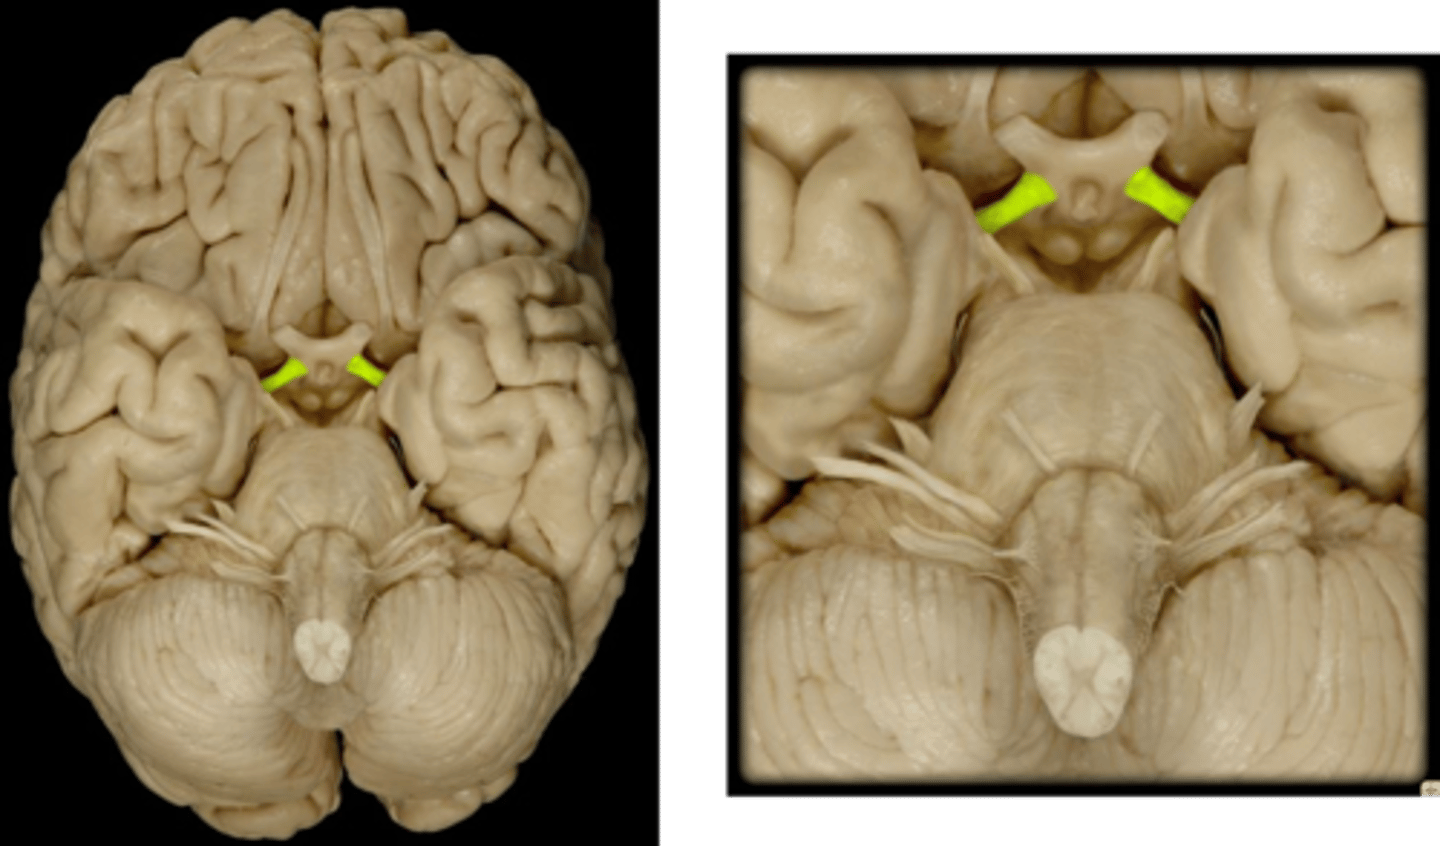

anterior commissure

White matter tract that crosses the third ventricle. Located just anterior to the thalamus. connects parts of the frontal+temporal lobes of the 2 hemispheres.